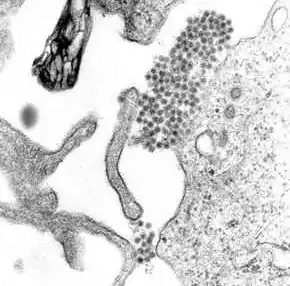

Once inside the skin, dengue virus binds to Langerhans cells (a population of dendritic cells in the skin that identifies pathogens).[48] The virus enters the cells through binding between viral proteins and membrane proteins on the Langerhans cell, specifically, the C-type lectins called DC-SIGN, mannose receptor and CLEC5A.[32] DC-SIGN, a non-specific receptor for foreign material on dendritic cells, seems to be the main point of entry.[35] The dendritic cell moves to the nearest lymph node. Meanwhile, the virus genome is translated in membrane-bound vesicles on the cell's endoplasmic reticulum, where the cell's protein synthesis apparatus produces new viral proteins that replicate the viral RNA and begin to form viral particles. Immature virus particles are transported to the Golgi apparatus, the part of the cell where some of the proteins receive necessary sugar chains (glycoproteins). The now mature new viruses are released by exocytosis. They are then able to enter other white blood cells, such as monocytes and macrophages.[32]